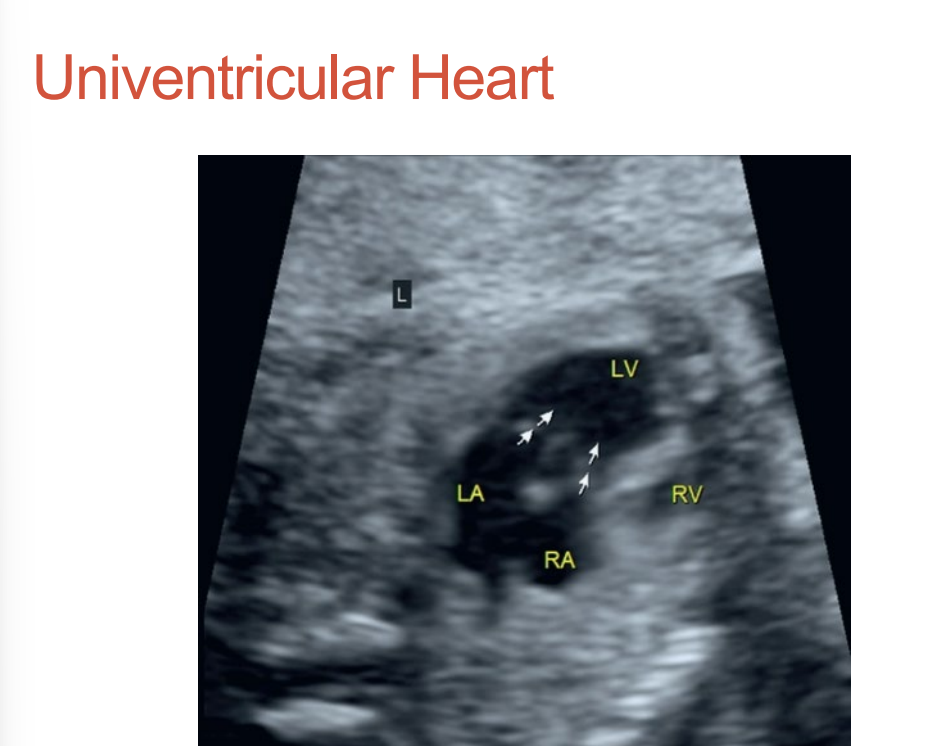

Univentricular Heart, Aka know as what?

Aka single ventricle •

3 chambers – two atria and a single ventricle •

Rare condition

Univentricular heart

Any CHD where two inflow valves empty into one ventricle •

May have a second small ventricle •

May have common valve •

Called a “Y” type circulation

Univentricular Heart • Associations name 3

heterotaxy syndrome •

coarct of the aorta •

Transposition of the great arteries